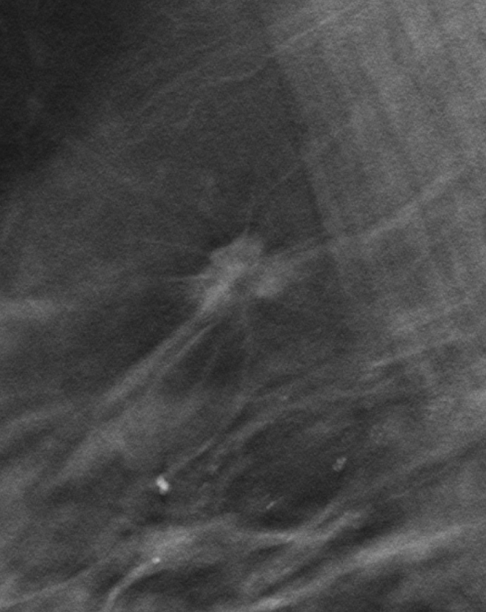

Томосинтез – аналог компьютерной томографии. Это послойное изображение молочных желез. Конечно, лучевая нагрузка при этом возрастет, но незначительно. Также увеличивается польза от этого исследования, ведь у врача появляется возможность послойно, толщиной в 1 мм, изучить весь объем молочных желез. Высокая маммографическая плотность для томосинтеза уже не является таким препятствием, как для аналоговой или цифровой маммографии.

Рис.3 Томосинтез: рак правой молочной железы